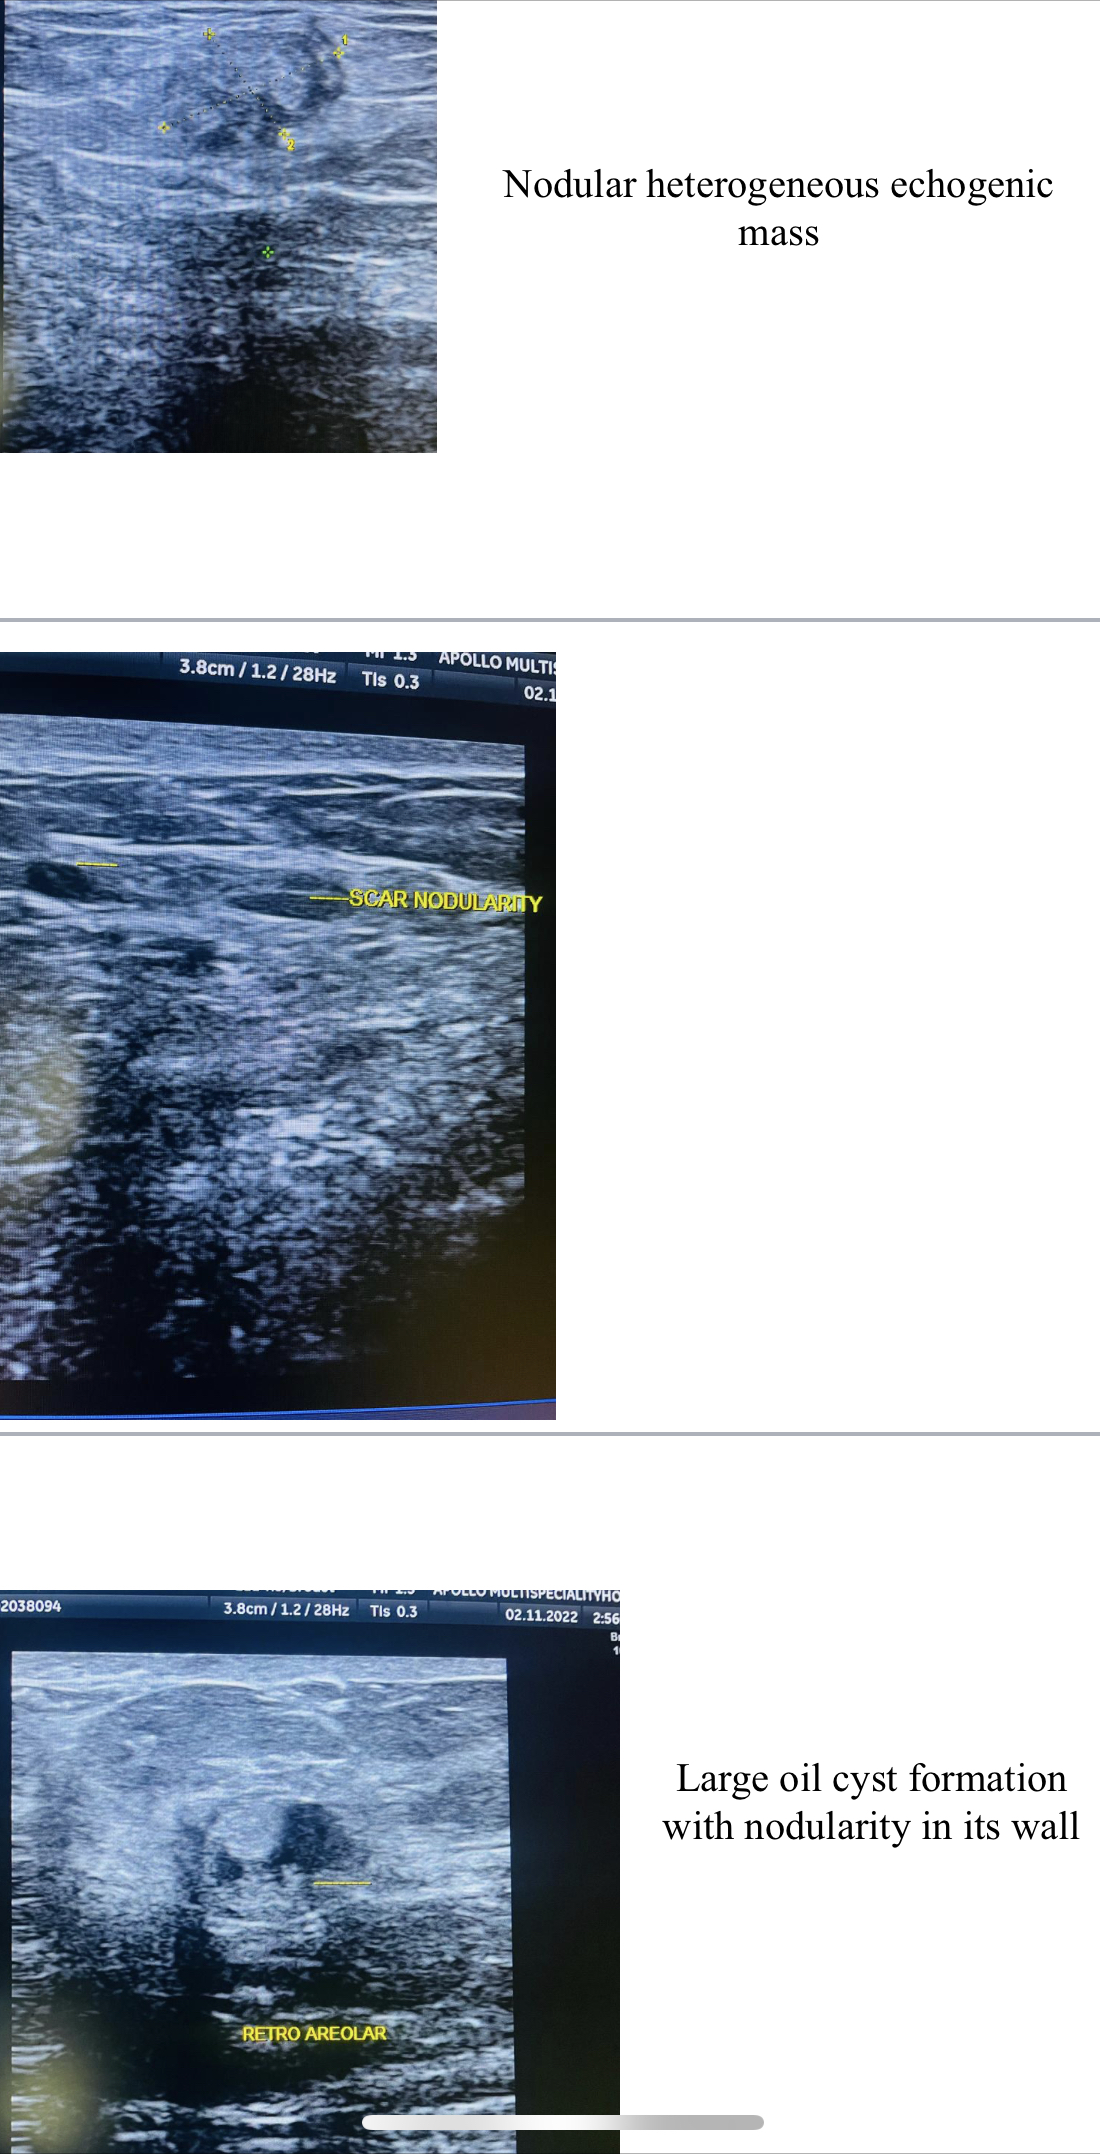

36 years old female with a history of lump left breast for 3 months wi...

Read More